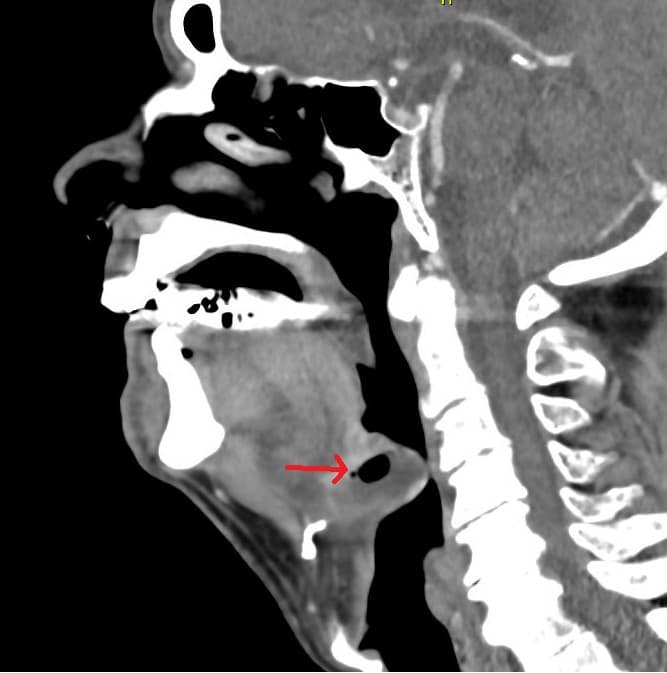

Patienten blev indlagt i intubationsberedskab på intensivafdeling og modtog intravenøs behandling med cefuroxim og steroid. Grundet uændrede forhold dagen efter blev der foretaget CT med kontrast, der viste højresidig PTA samt sænkningsabsces til vallecula epiglottica. Efter tonsillektomi og udtømning af absces blev patienten symptomfri og kunne udskrives.

Absces i vallecula epiglottica er en sjælden og potentielt livstruende tilstand, der kan føre til akut kompromitterede luftveje [1-3]. Sænkningsabscesser kan opstå som komplikation til PTA [3]. Klinisk differentiering mellem simpel, øvre luftvej-infektion og potentielt respirationstruende tilstand er inspiratorisk stridor, synkebesvær (spytflåd) og hurtig forværring [1,2].